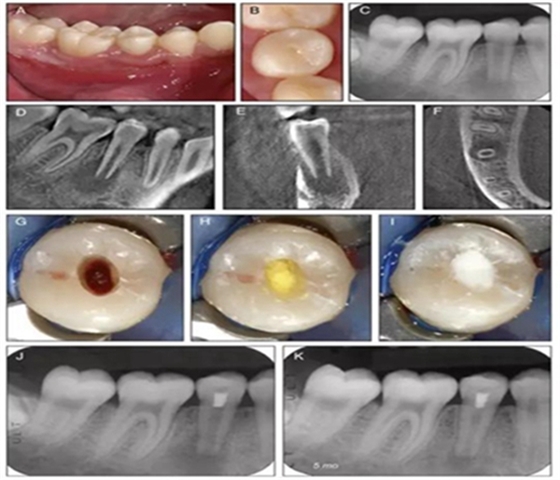

原則上年輕恒牙的牙髓治療應(yīng)盡可能以保存活髓的方式以便不影響牙根繼續(xù)發(fā)育。本文3個病例均描述了根尖尚未發(fā)育完成的下頜前磨牙被確診為牙髓壞死伴有大面積根尖病損,治療過程中在根管內(nèi)發(fā)現(xiàn)了部分活髓,而采用活髓切斷后都取得了很好的療效。